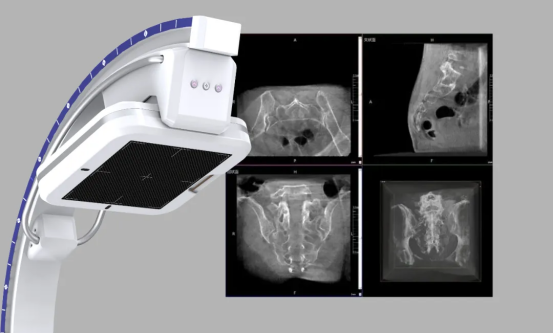

As a provincial-level regional medical center, Ningde Municipal Hospital has always focused on the core needs of clinical diagnosis and treatment, empowering precision medicine through the introduction of advanced equipment. By adopting Perlove Medical's flat-panel 3D C-arm, the hospital overcomes the limitations of traditional 2D imaging, making lesion localization and adjacent tissue identification clear at a glance, and providing entirely new imaging support for precise orthopedic care.

02 Wide Field of View — See Everything

The device is equipped with a Large FPD, capable of capturing the entire lumbar spine, bilateral sacroiliac joints, and unilateral pelvis in a single scan. This avoids repeated adjustments by the operator due to limited FOV, improving workflow efficiency and reducing radiation exposure from multiple scans.